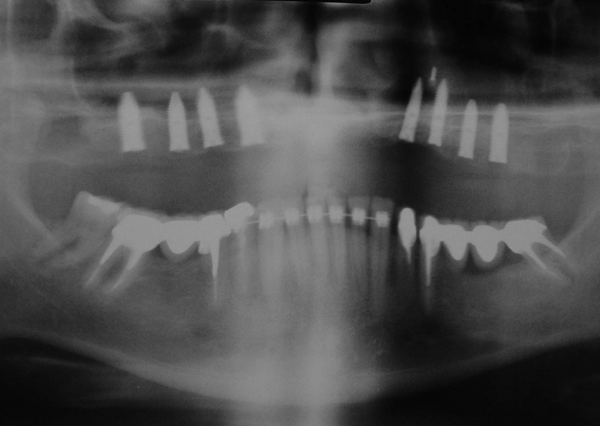

Raio X com prótese em porcelana com dentes individuais instalada - Clínica Cliniface

Raio X com prótese em porcelana com dentes individuais instalada